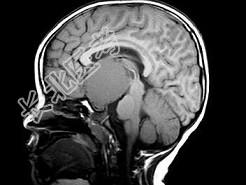

- 单项选择题女,8岁, 头痛、左侧肢体麻木十余天,根据所提供图像, 最可能的诊断是 ( )

A、表皮样囊肿

B、颅咽管瘤

C、垂体瘤

D、胶质瘤

E、蛛网膜囊肿